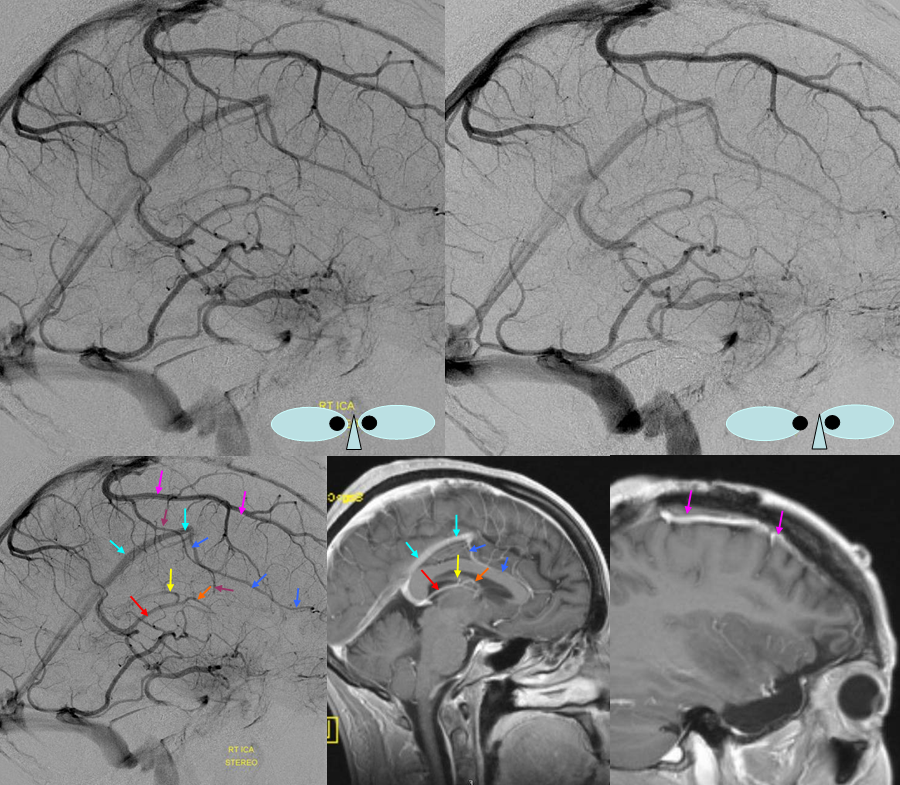

Below is a case of severe venous sinus thrombosis and secondary parenchymal venous infarcts

The explanation for the above tragic pattern is below. On the right, sigmoid and transverse sinuses are patent. However, the Labbe is hypoplastic, and majority of outflow used to go to the Trolard, into the now occluded SSS. There is no other effective way to go — the trolard tries to decompress via a left diploic vein, and convexity tries to access the deep venous system (which normally should not be well-seen in setting of hypoplastic right A1 segment). The left situation is much better, as well-developed superficial sylvian veins drain into the patent Cavernous Sinus. Thus, despite thrombosis of the left transverse and sigmoid sinuses, the left hemisphere is doing better, while the right one, which has patent transverse and sigmoid sinuses, is devastated.

Post venous thrombectomy — with limited results. Note presence of same left diploic vein as seen in right ICA injection, and connection between the distal superior sagittal sinus and the deep venous system via the inferior sagittal sinus.